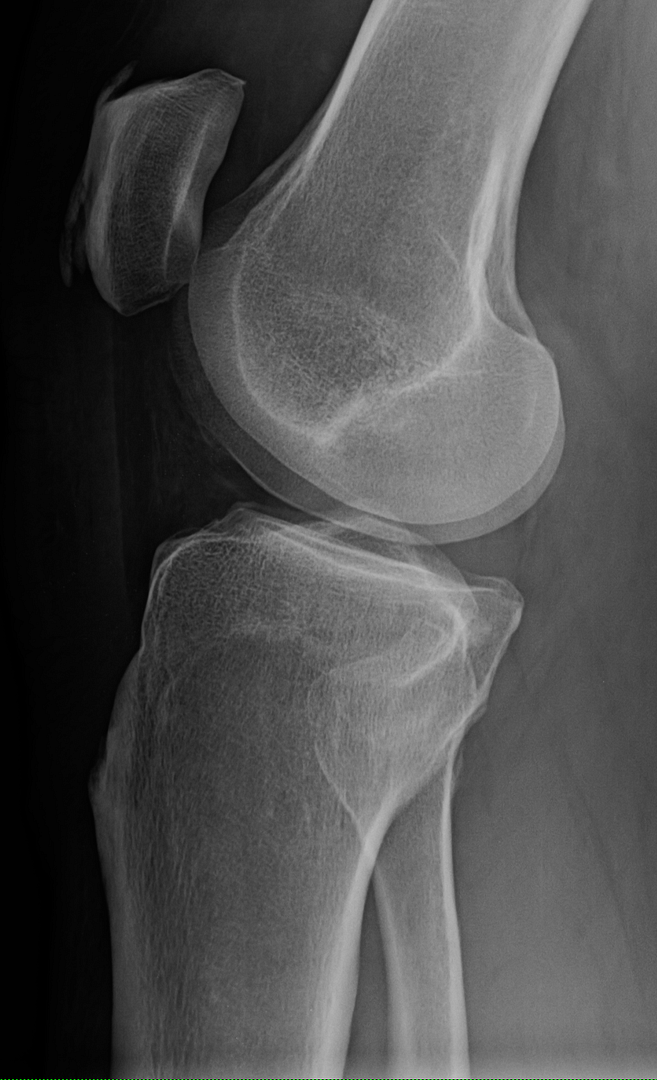

Your sunrise pateler views (bottom knee cap floating in space view) are worrying. You are developing bone avulsions (the part where it looks like it is separating) most likely due to impact injury coupled with straining tendons. You got to start wearing knee pads for what ever you are doing that is impacting them. If that continues in the same path, even walking will be a chore.

On the lateral view I can see see a section of calcification on the anterior aspect. ................... The worrying part is just bellow the calcium I see a region that looks like a chip fracture or an older one. Its the diagonal line with the offset. Of course, I could just be nitpicking and just seeing something that is an optical illusion.